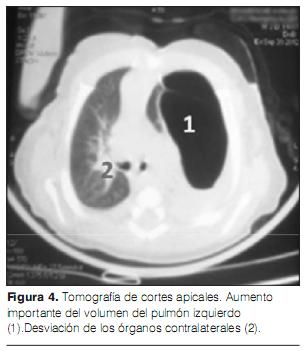

Ante este cuadro clínico, se realizan una radiografía de frente estándar (figura 1) y una TAC torácica (figuras 2, 3 y 4). La ecografía cardiaca y la ecografía abdominal son normales.

El TAC torácico es el examen complementario de elección para apoyar el diagnóstico, establecer la topografía exacta y precisar su ubicación así como las características de la distensión pulmonar y excluir también posibles anomalías mediastinales asociadas. El lóbulo afectado aparece bajo la forma de una zona pulmonar sistematizada e hipodensa, con arquitectura pulmonar a menudo conservada. El lóbulo superior izquierdo es el más afectado, seguido por el lóbulo medio derecho y el lóbulo superior derecho, con 41%, 34% y 21% respectivamente. Los lóbulos inferiores raramente padecen con menos de 3% (3,23). También puede asociarse atelectasia de las zonas pulmonares subyacentes. Se han descrito algunos casos de ELC bilateral, pero son extremadamente raros (13,24).